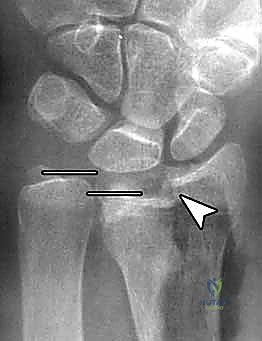

يعتمد الدكتور محمد هطيف على أحدث التقنيات التشخيصية، حيث يبدأ بـ الأشعة السينية (X-rays) في وضعيات متعددة. وفي حالات الكسور المعقدة التي تمتد إلى داخل المفصل، يتم إجراء تصوير مقطعي محوسب (CT Scan) لبناء صورة ثلاثية الأبعاد للكسر، مما يساعد في التخطيط الجراحي الدقيق.

6. الفحص النهائي والإغلاق

يتم إجراء فحص أخير بالأشعة للتأكد من المحاذاة المثالية للكسر وأطوال المسامير (لضمان عدم بروزها واحتكاكها بالأوتار الخلفية). بعد ذلك، يتم خياطة الأنسجة والجلد بخيوط تجميلية ووضع ضمادة معقمة.